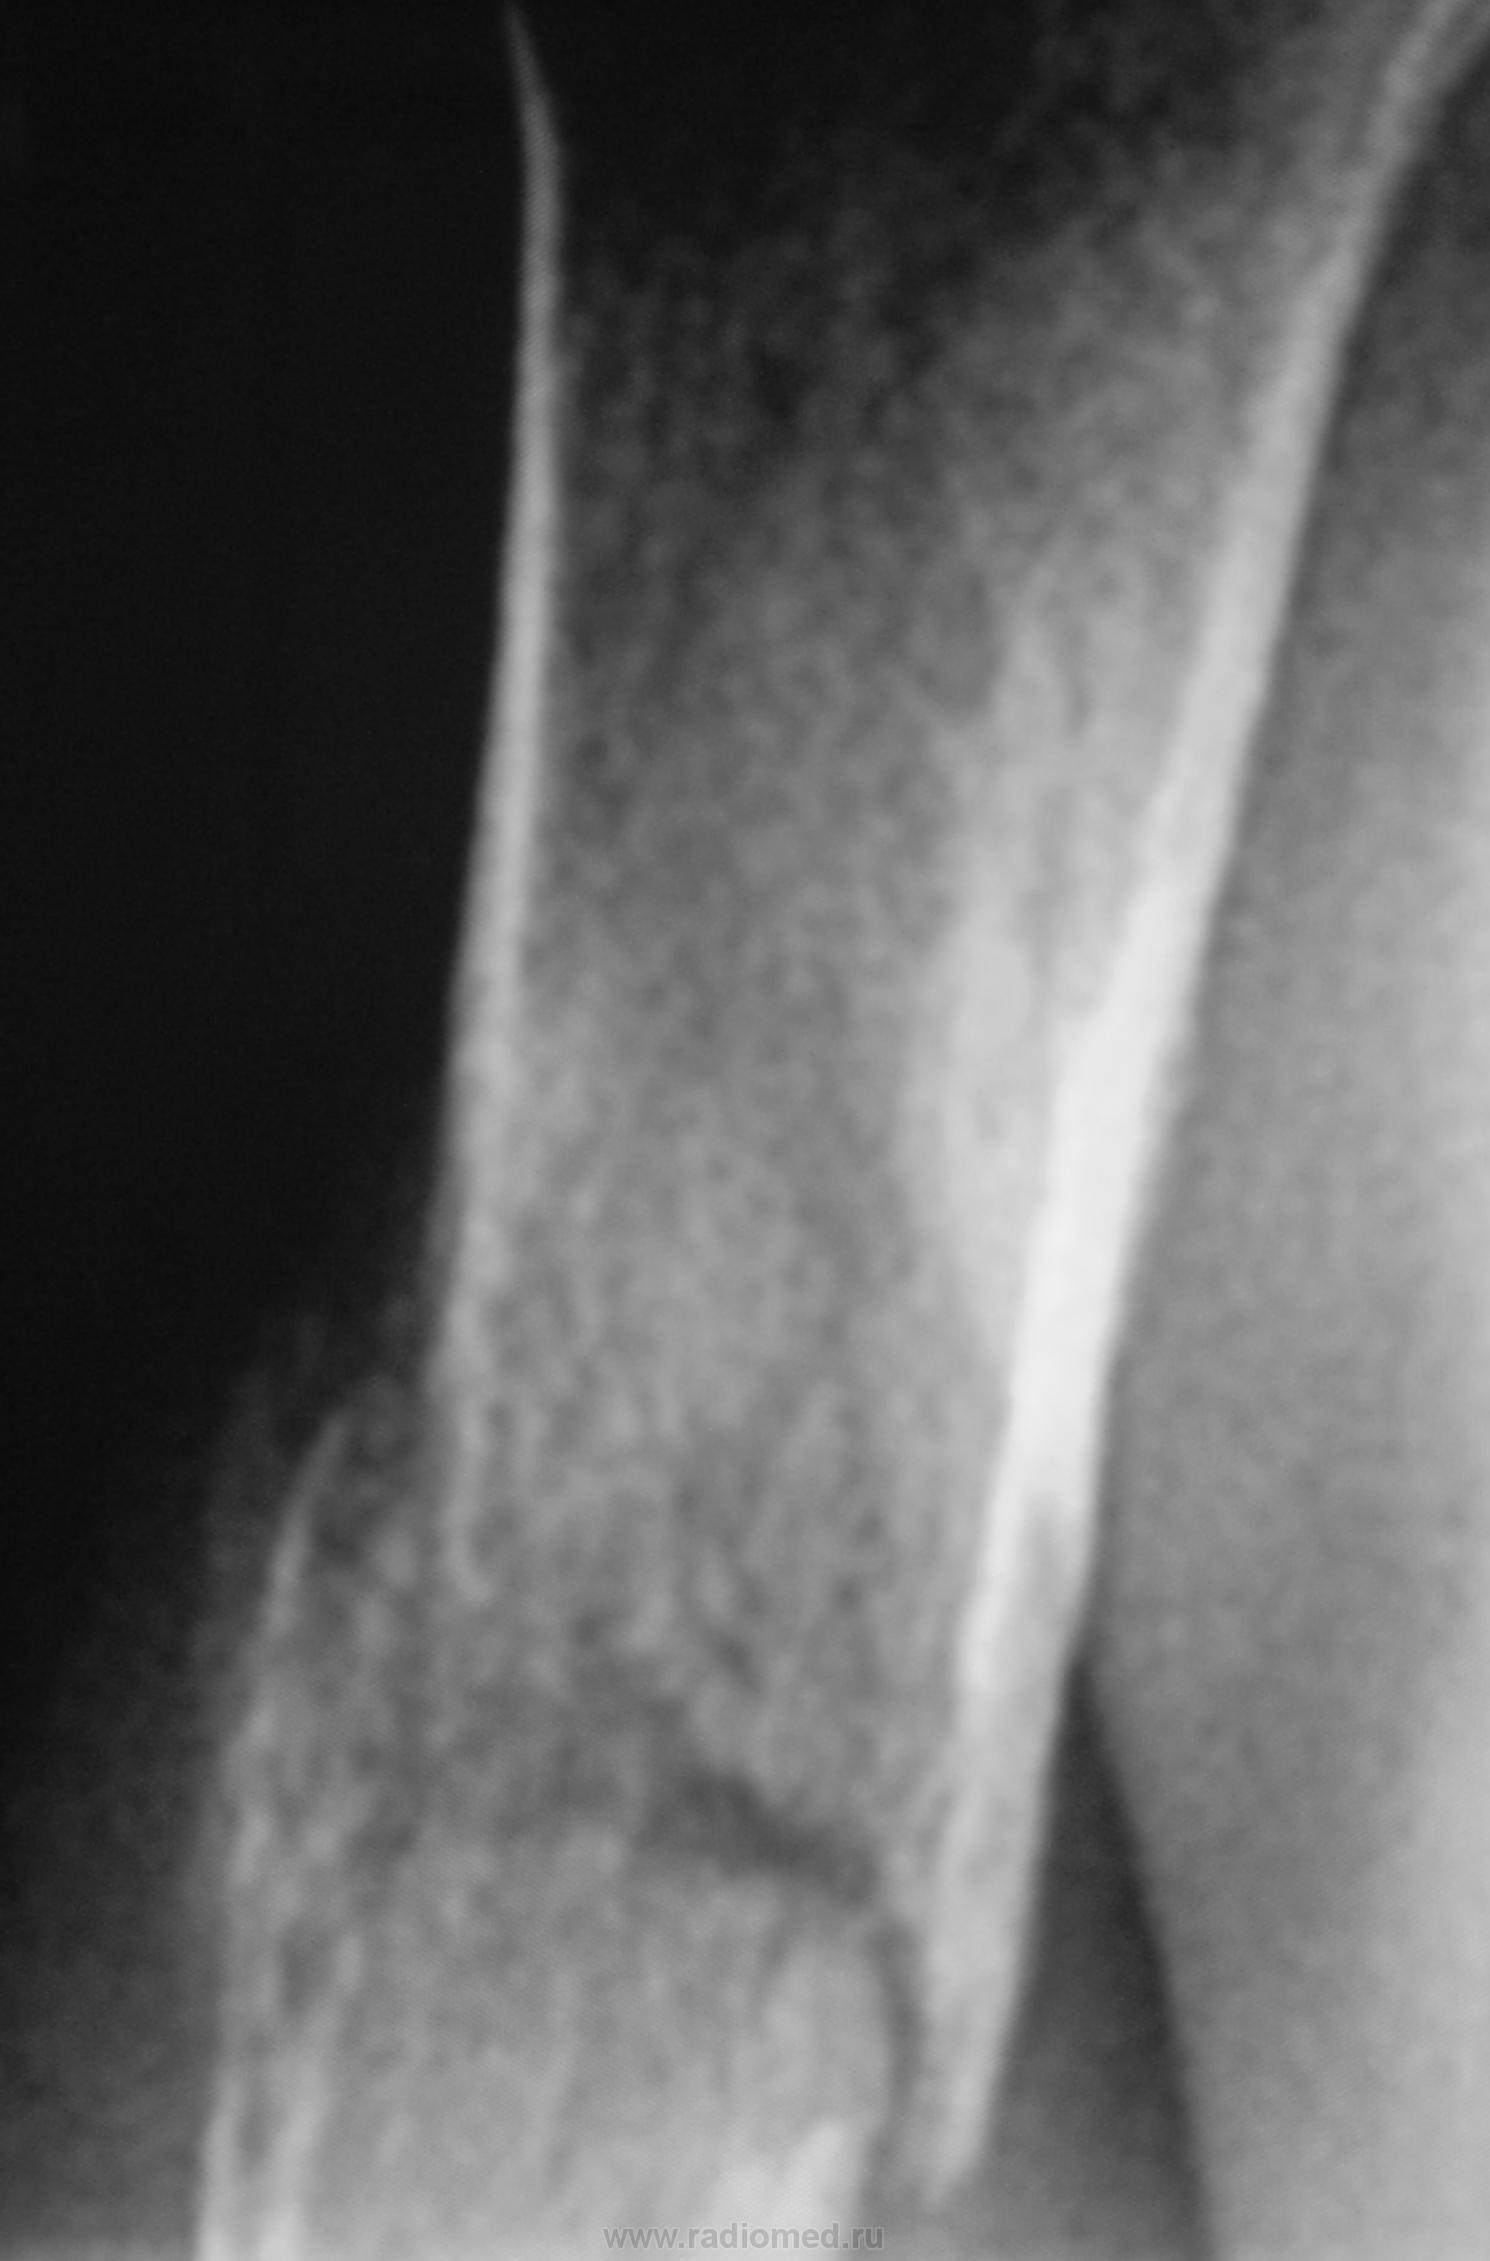

Случай 4.